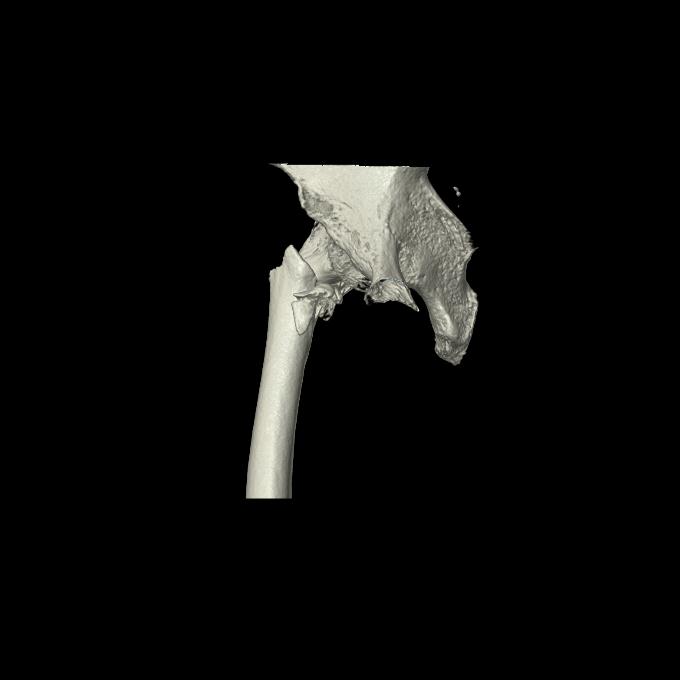

110286 2/17 股関節 2R 74歳女性 右人工骨頭

102903 股関節 2R 1/28 +股関節 2R 1/29 78歳女性 左人工骨頭

82084 1/14 1/20 股関節 2R 78歳男性 右人工骨頭

102811 1/13 股関節 2R 1/19 2R 80歳女性 右DHS